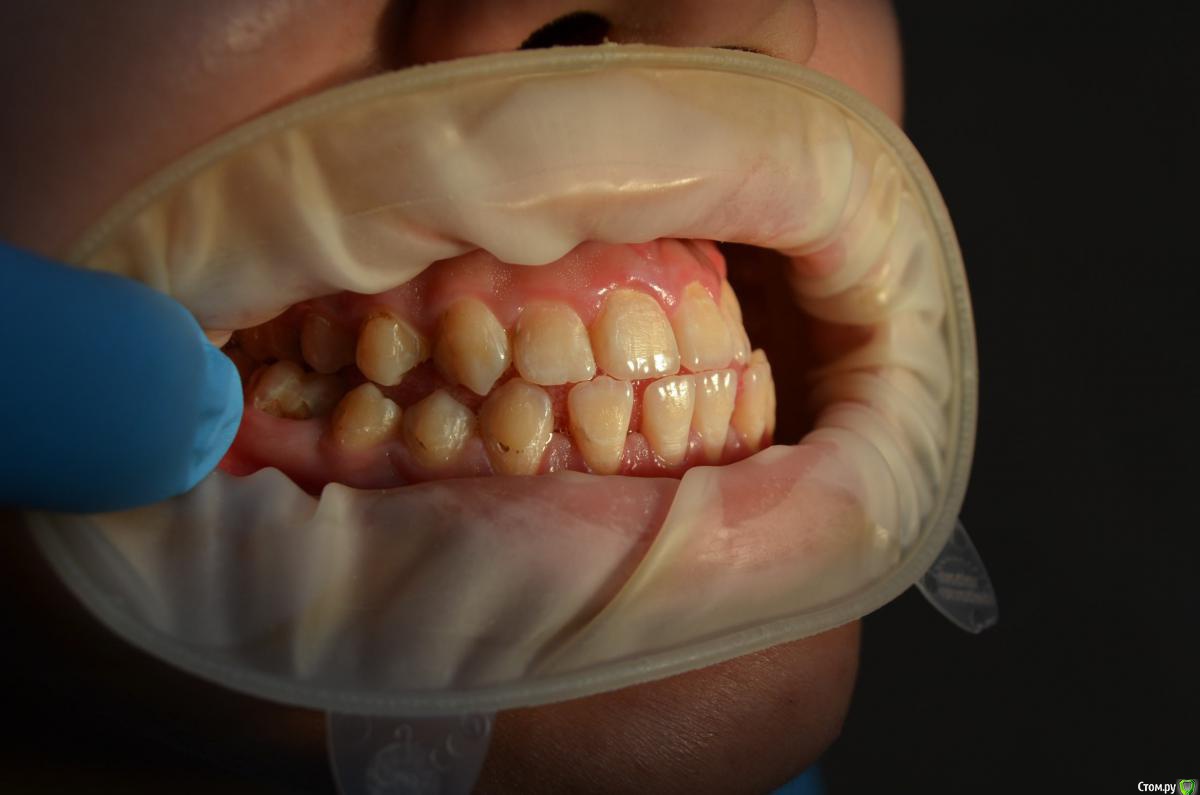

Пациентке 16 лет носила брекеты 4 года (переносила), нижний фронт зубов подвижен, слизистая воспалена, тремы на н.ч, множественный кариес под брекетами после снятия, сейчас на этапе эндолечения. Помогите советами как правильно и с чего начать , на в.ч. поставил ретейнер, на нижней пока идет терапевтическое лечение. ТРГ нету